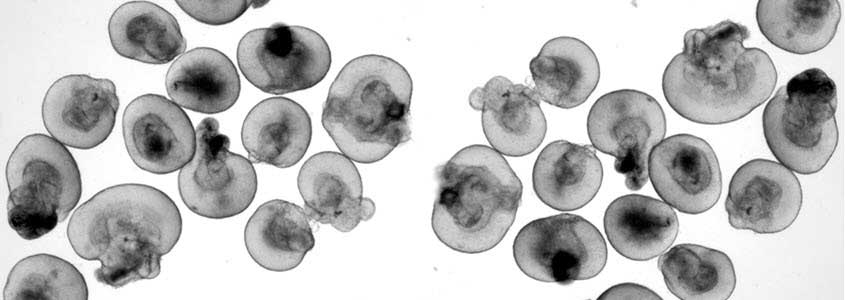

Saving and Restoring Sight In Macular Degeneration Patients​

Developing innovative stem cell-based technologies to both prevent and cure AMD

It is expected that by 2040, 288 million people worldwide will suffer from age-related macular degeneration (AMD). Despite significant efforts, there are still no therapies to prevent or cure AMD.

In the ideal scenario, patients would be diagnosed at the very early stages of the disease and treated immediately to prevent the disease's progression and the death of the cells in the retina. Unfortunately, our ability to do so is critically limited by the lack of understanding of the early pathophysiological events leading to AMD. This, in turn, is a consequence of the lack of experimental models capable of fully recreating the characteristics of the human disease. On the other hand, the lack of preventive treatments has led to an increasing number of patients with advanced stages of AMD and severe vision loss. Addressing the needs of these patients would require a treatment aimed at regenerating the cells already lost to the disease rather than preventing their death.

At CellSight, one of our goals is to develop innovative stem cell-based technologies to both prevent and cure AMD. â€‹